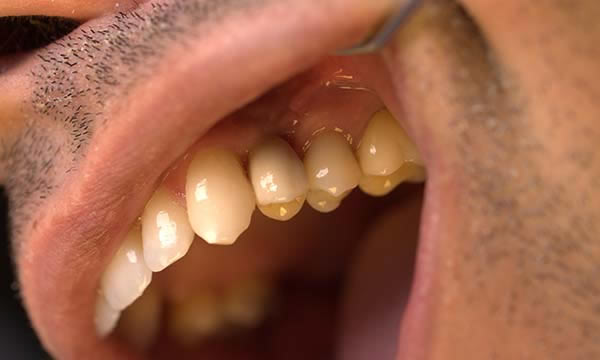

Case B

This gentleman had lost his heavily restored UL4 and decided to close the space with an implant retained crown. The thin buck-palatal width required careful placement to avoid fenestration bucally. A tooth bourn position guide was used to place the implant predictably and within the aesthetic envelope. The implant was restored after three months of osseointegration with a bonded crown.

After Treatment